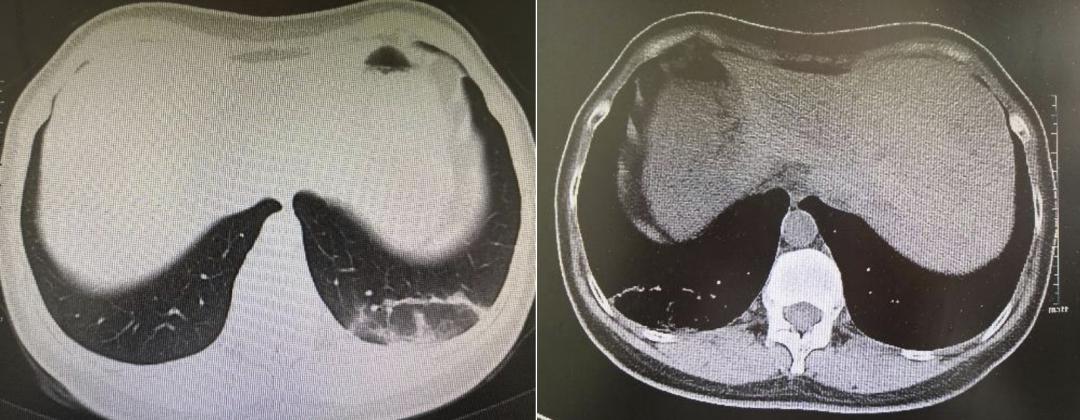

回顾全病程,对该患者经前期仔细问诊和有效、迅速的分析与检查,最终诊断为:鹦鹉热支原体肺炎、血小板减少、低钾血症。我们调整抗感染治疗方案为:莫西沙星+多西环素抗感染、调整电解质等对症治疗,后体温恢复正常,复查胸部CT,提示肺部病灶较前明显吸收(图2)。

图2.2022年5月26日患者肺部CT影像